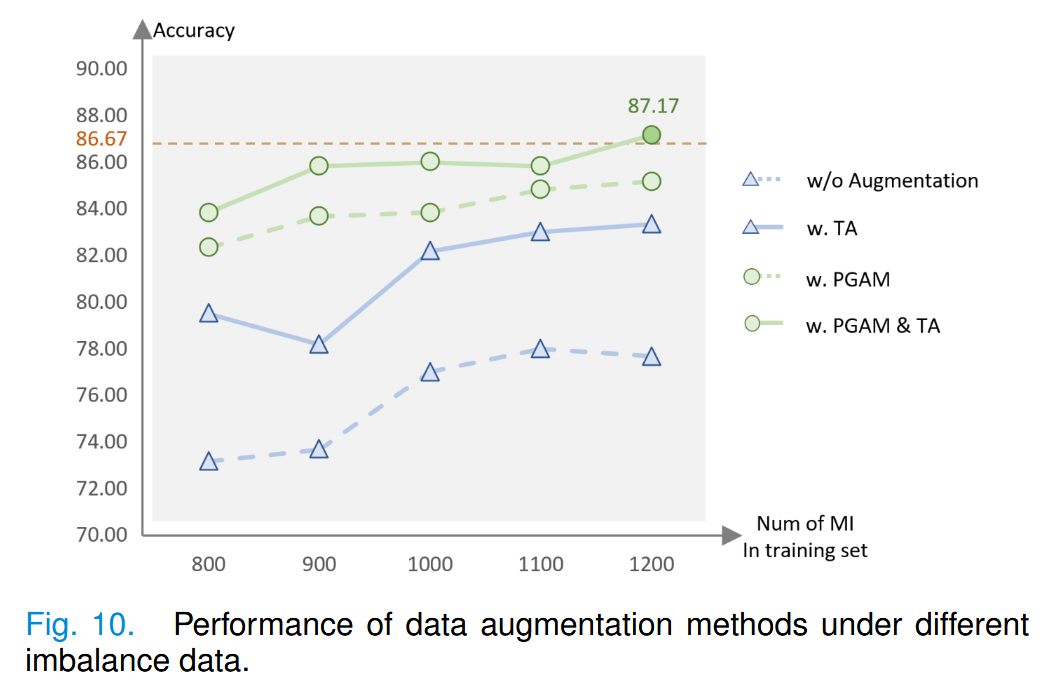

此外,为了证明我们的方法在解决数据不平衡问题上的能力,我们在恶性数据不平衡的情况下进行了多次不同稀缺程度的实验。具体而言,通过将训练集中的恶性数据数量分别限制为800、900、1000、1100和1200,并在有足够良性数据的情况下进行实验,结果如图10所示。

图中的橙色虚线显示了未进行人工移除时分类器的准确率(3932 BI,3666 MI)。

可以看出,我们的方法始终优于TA。一旦恶性数据的比例达到一定程度(1200:3932),这两种增强方法的结合使分类器的性能超过了使用真实且平衡数据训练的模型。